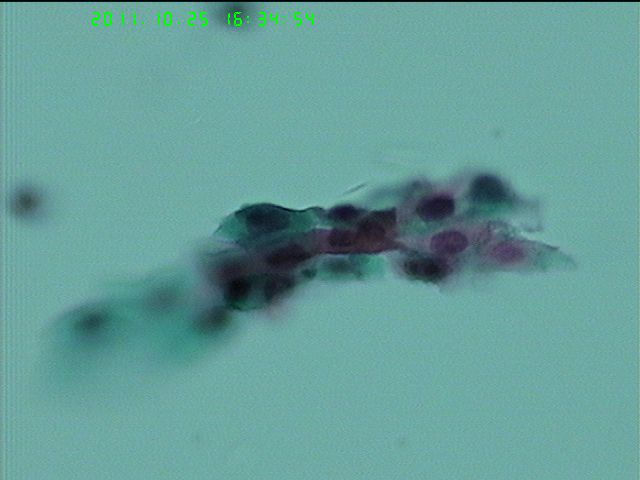

62岁女性  停经  有问题吗?细胞量稀少

老年性病人,萎缩性背景的病例,出现LSIL的病例是不多见的。

萎缩的时候,细胞很难成长到表层或者浅表层阶段,感染的HPV病毒颗粒也就没有办法完成整个生活史,因此一般不见典型的挖空细胞 萎缩性背景下,需要鉴别的为高核浆比的副基底层和HSIL,凋亡细胞与小的角化性鳞癌细胞。

此例有不少高核浆比,核异型,胞浆明显角化的细胞,报告时需谨慎,如果没有把握,ASC-H是不错的选择。

可见高核浆比细胞,核深染,核膜不规则,考虑到是老年人 报ASC-H比较恰当,达到活检目的即可。

组织学是CA